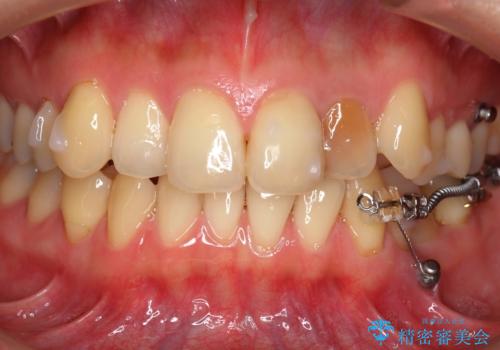

引っ張り出すことはマウスピース矯正では難しい為、埋まっている歯を並べるスペース確保と、引っ張り出すのに、ワイヤーを用いた部分矯正を行なっています。

上の歯はマウスピース矯正で、奥歯を後ろに下げて、左のかみ合わせのズレを直しています。